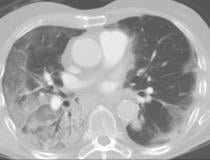

This photo gallery shows the variety of radiological presentations of COVID-19 (SARS-CoV-2) in medical imaging, including computed tomography (CT), radiograph X-rays, ultrasound, echocardiograms and magnetic resonance imaging (MRI). The radiology images show examples of typical COVID pneumonia in the lungs and the numerous complications the virus causes in the body in multiple organs, including the brain, kidneys, heart, abdomen and vascular system.

Ultrasound, especially hand-held ultrasound imaging devices, have become a primary imaging modality for novel coronavirus because of the ease to bag the device and sterilize it after use. CT and mobile X-ray systems are also used as front-line imaging systems for COVID-positive or suspected COVID patients.